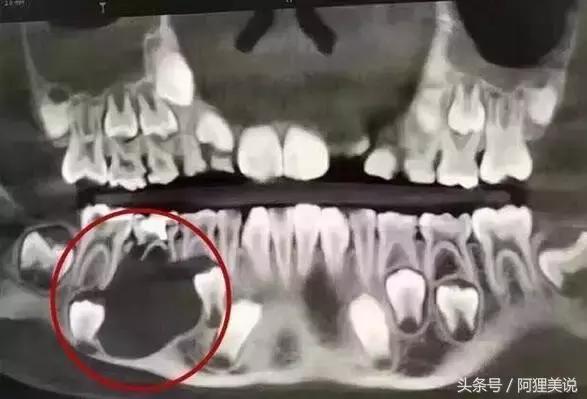

5龄童20颗乳牙全部蛀光

嘴里20颗乳牙,全部龋坏。

一开始,田田患的是“奶瓶龋”,

这种蛀牙往往是因为长期使用奶瓶造成的,

因为牛奶、母奶、果汁及糖水等,

都含有不同成分可发酵醣类,

经变形链球菌利用之后而产生酸,

长时间滞留在牙齿周围,

造成牙齿表面脱钙。

发病率最高的是窝沟龋,

约占儿童龋齿的80%,

而“六龄齿”(即第一恒磨牙)就是窝沟龋的好发部位。